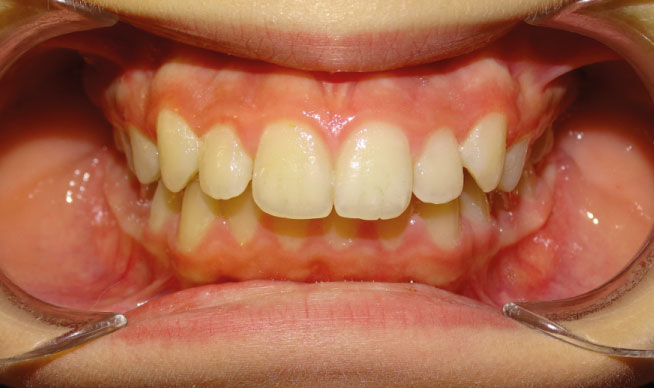

la présence d’une supraclusion, cela signifie que le recouvrement des incisives inférieurs par les incisives supérieures est trop important. Autrement dites, les dents du dessus « cachent » celles du bas, c’est pourquoi on parle aussi de recouvrement dentaire. La supraclusion se manifeste par un recouvrement trop important des incisives inférieurs par les incisives supérieures. Les dents du dessus « cachent »les dents du bas. Ce trouble est fréquent et est aisément traitable grâces aux nouvelles techniques d’orthodontie. Grâce aux nouvelles techniques d’orthodontie, le traitement est facilité́. Il n’est plus nécessaire de porter des « casques » externes et il est très rare d’extraire des dents. Le port de rackets (les « bagues ») permet de résoudre le problème chez l’enfant et l’adulte.